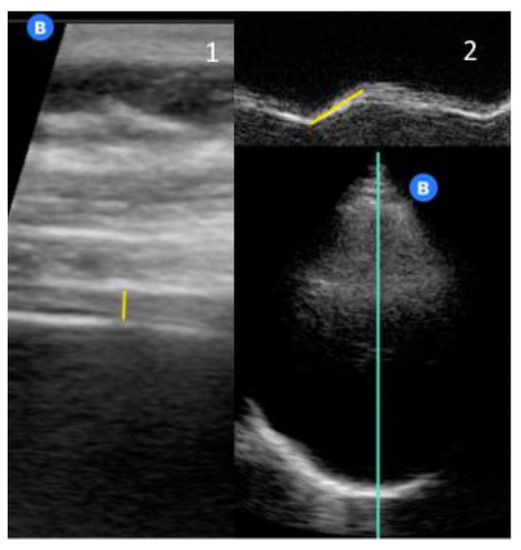

2. Materials and Methods